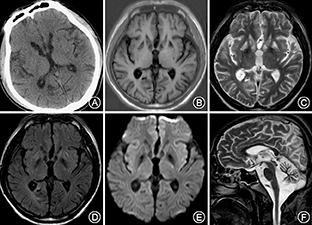

患者男性,38岁,因"头晕16年,走路不稳伴视物模糊12年,发作性意识丧失伴肢体抽搐8年,反应迟钝、全身无力3年"于2014年9月收入我科。2007年,患者曾因"脑外伤"昏迷数日,于外院进行治疗,曾被诊断为"脊髓小脑变性、齿状核-路易体-苍白球-红核变性"等疾病,行相关基因检测均未发现致病突变。否认其他既往病史,26岁结婚,育有1子,身体健康。父亲体健,母亲身材矮小,视力及听力均下降;2位姐姐及1位哥哥均体健。入院体检:体重51 kg,身高160 cm,一般状况可,体检欠配合。弓形足,内科系统体检无异常;意识清楚,反应迟钝,记忆力及计算力减退;双侧视敏度下降,左侧0.5,右侧0.3(国际标准视力表),视盘边界清,色暗黄,视网膜可见骨细胞样色素沉着,双耳听力下降,构音障碍;四肢肌张力略低,肌力Ⅳ级,腱反射减低;四肢振动觉略有减退,痛觉及关节位置觉尚可;自主运动缓慢,双侧指鼻试验欠稳准,双侧跟膝胫试验欠稳准,闭目难立征阳性,共济失调步态;双侧巴宾斯基征、双侧夏多克征阴性;脑膜刺激征阴性。一般实验室检查:同型半胱氨酸16.3 μmol/L,抗甲状腺球蛋白抗体205 U/ml,抗甲状腺过氧化物酶抗体59.67 U/ml,甲状腺球蛋白0.05 ng/ml,甘油三酯1.9 mmol/L,铜蓝蛋白672 U/L,余血液检查未见异常。脑脊液检查:脑脊液蛋白0.50 g/L,余未见异常。血乳酸检测:患者行乳酸-丙酮酸最小量运动试验,多项比值异常,具体结果详见表1。影像学检查:患者自2006—2014年多次行头颅CT及MRI检查,其中本次入院行头颅CT及MRI示小脑及脑干萎缩,双侧基底节及皮质下多发缺血变性灶及软化灶(图1)。眼底照相示:视盘边界清,色暗黄,血管走行僵直呈一致性狭窄;眼底色泽污秽,可见骨细胞样色素沉着(图2),提示视网膜色素变性。